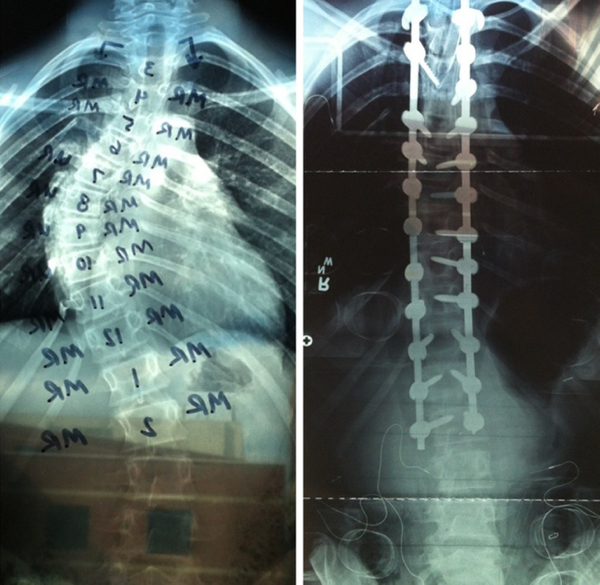

› Awesome › Humanity, Inspirational People who vowed to change something about themselves are killing it (15 Photos) Adam Jan 29, 2023 Add Favorite 1380 63 0 1 “My little brother just had surgery on his spine. Here are some before/after X-ray pics.” LoganPS